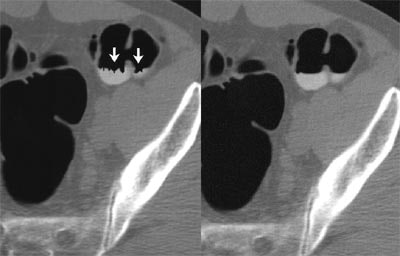

"Although originally intended to reduce or eliminate the need for colon purgation, electronic cleansing is also of benefit in the prepared colon," Pickhardt and Choi wrote. "Removing opacified residual fluid digitally allows 3-D evaluation of colonic mucosa that would have otherwise been obscured," enabling the detection of neoplasia submerged in fluid. The picture is not perfect, however. Rather than clearly depicting the submerged mucosa, the linear artifact where air-fluid level interfaces with the colon wall "has been likened to residue that remains in (a) tub after (a) bath," they wrote.

| Electronic cleansing of contrast-opacified luminal fluid on 3-D virtual colonoscopy in an asymptomatic 65-year-old man undergoing colorectal cancer screening. Uncleansed (left) and cleansed (right) images from the same endoluminal perspective show increase in visualized mucosal surface after digital subtraction of residual fluid. Characteristic linear artifact where air-fluid level interfaces with colon wall (arrows, right) has been likened to residue that remains in a tub after a bath. Images and caption used with permission of the American Roentgen Ray Society from AJR, © September 2003, Vol. 181:3, pp. 799-805. |